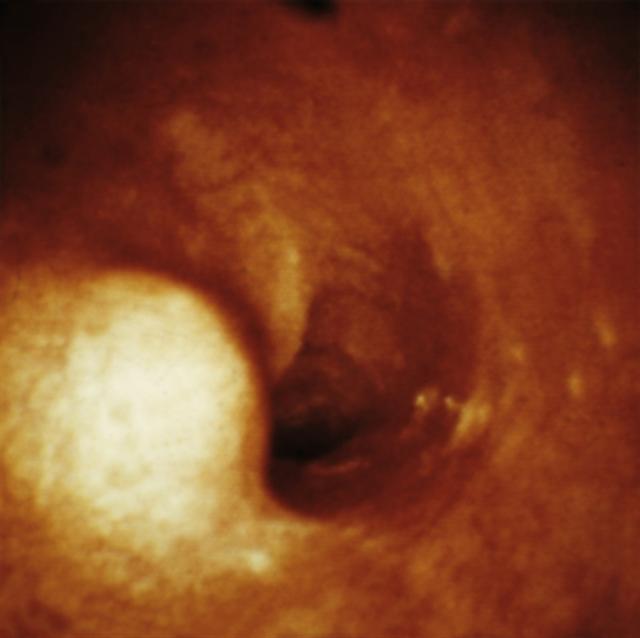

Рис. 12. Эндоскопическаая картина липомы пищевода.